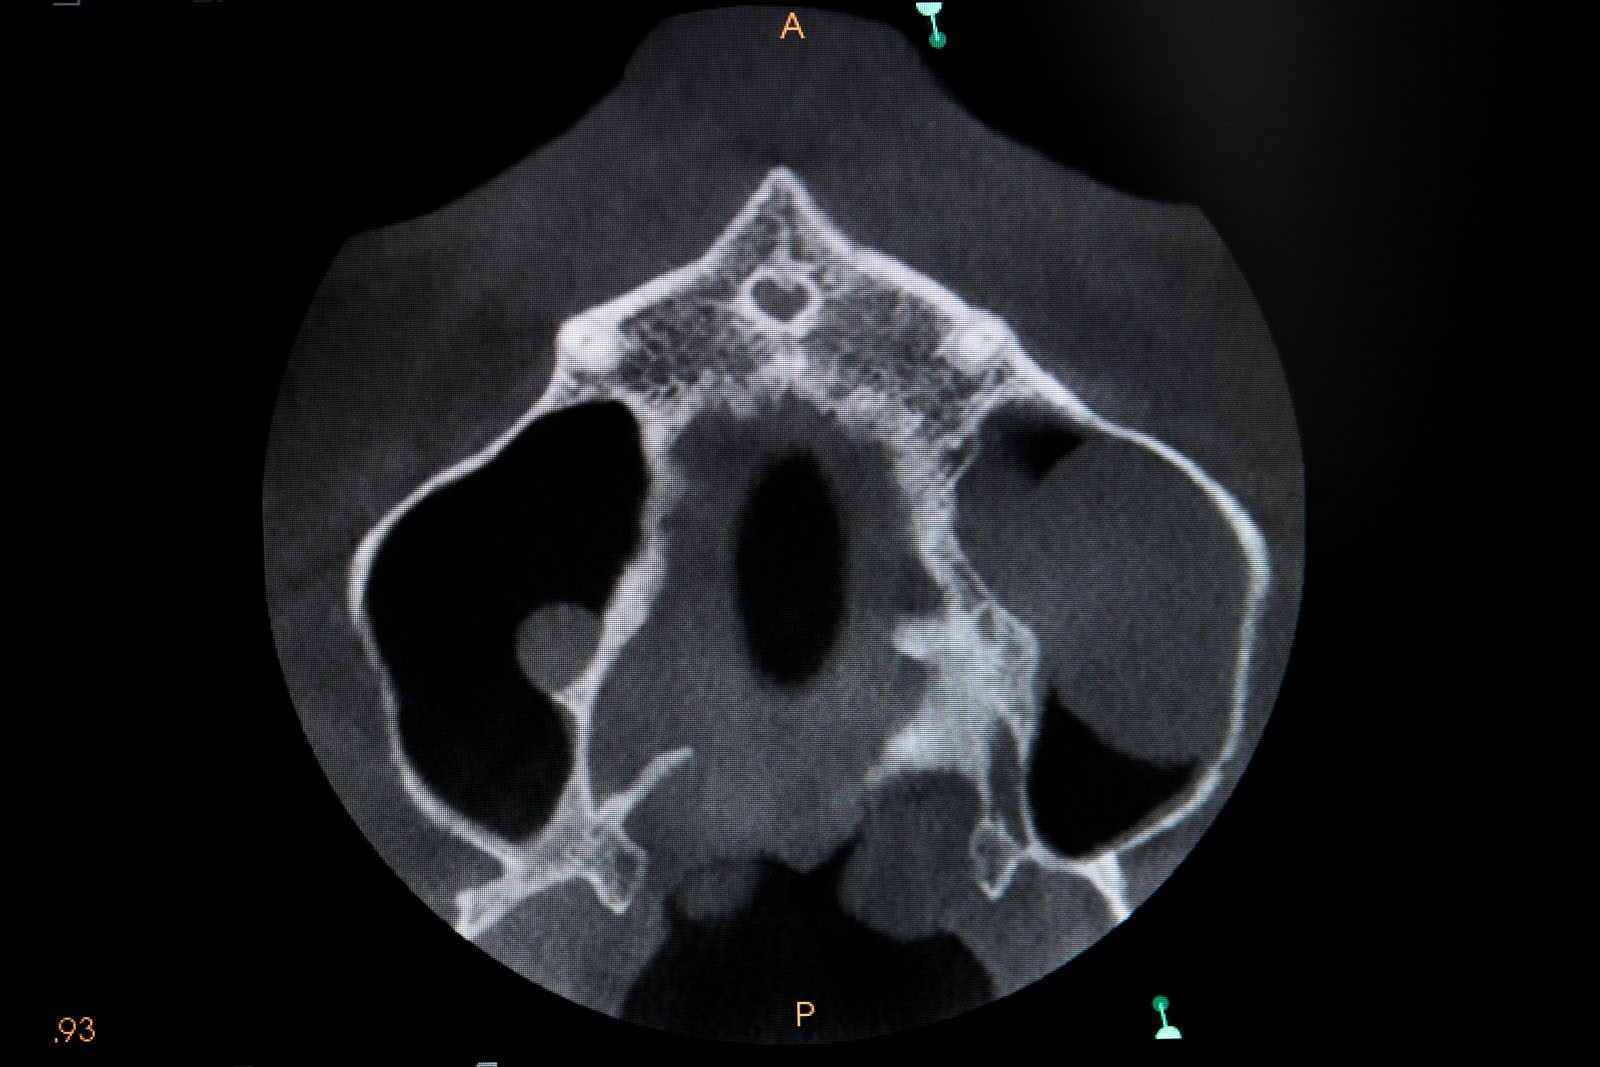

- Diagnostyka obrazowa, uwzględniająca dokładne badanie radiologiczne zatok szczękowych oraz tkanki kostnej pod kątem umieszczenia w niej implantów

Tomografia komputerowa szczęk CT – ocenia stan i czystość zatok szczękowych, stopień skrzywienia przegrody nosa, drożność otworu zatoki szczękowej oraz anatomię tzw. zespołu ujściowo-przewodowego, od którego zależy długoterminowy efekt leczenia, kształt i wymiary kości jarzmowej.

Tomografia komputerowa stożkowa CBCT – ocenia wszystkie powyższe parametry anatomiczne, które przedstawia na trójwymiarowym obrazie.

- Kwalifikacja poprzez wyeliminowanie stanów zapalnych, deformacji i rozrostów w zatokach szczękowych

CBCT, które wybiórczo może okazać stan kości w pozostałej części zębodołowej szczęk, stan oraz powietrzność zatok szczękowych, co jest istotnym parametrem kwalifikującym pacjenta do zabiegu operacyjnego, stan przegrody nosa

CT tomografia komputerowa liniowa ukazująca stan całości zatok okołonosowych, drzewo małżowinowe, stopień skrzywienia przegrody nosa, stopień obturacji naturalnego otworu łączącego jamę nosa z zatoką szczękową – rozworu zatoki szczękowej.